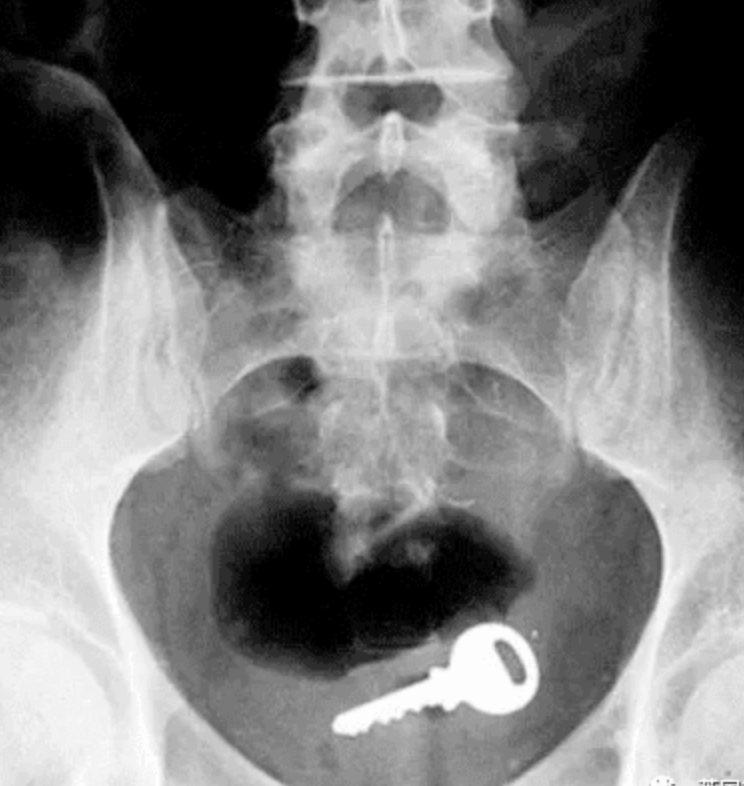

钥匙